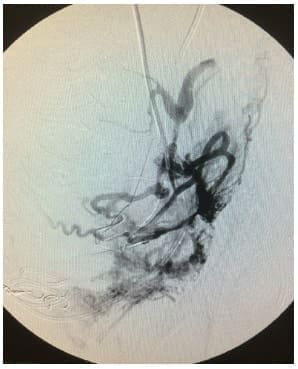

La imagen angiográfica debe hacerse con sustracción digital en fase arterial temprana y tardía, para poder observar las ramas arteriales anómalas en sacacorchos pseudotumorales 22 (figura 4).

Figura 4. Vasos pseudotumorales anomalos y multiples que nutren la placenta percreta.

En los casos de acretismo placentario, no solamente la embolización de las ramas uterinas controla el sangrado. Es muy importante evaluar la participación de otras arterias como pudendas, epigástricas, ováricas, sacras y obturatriz 23.